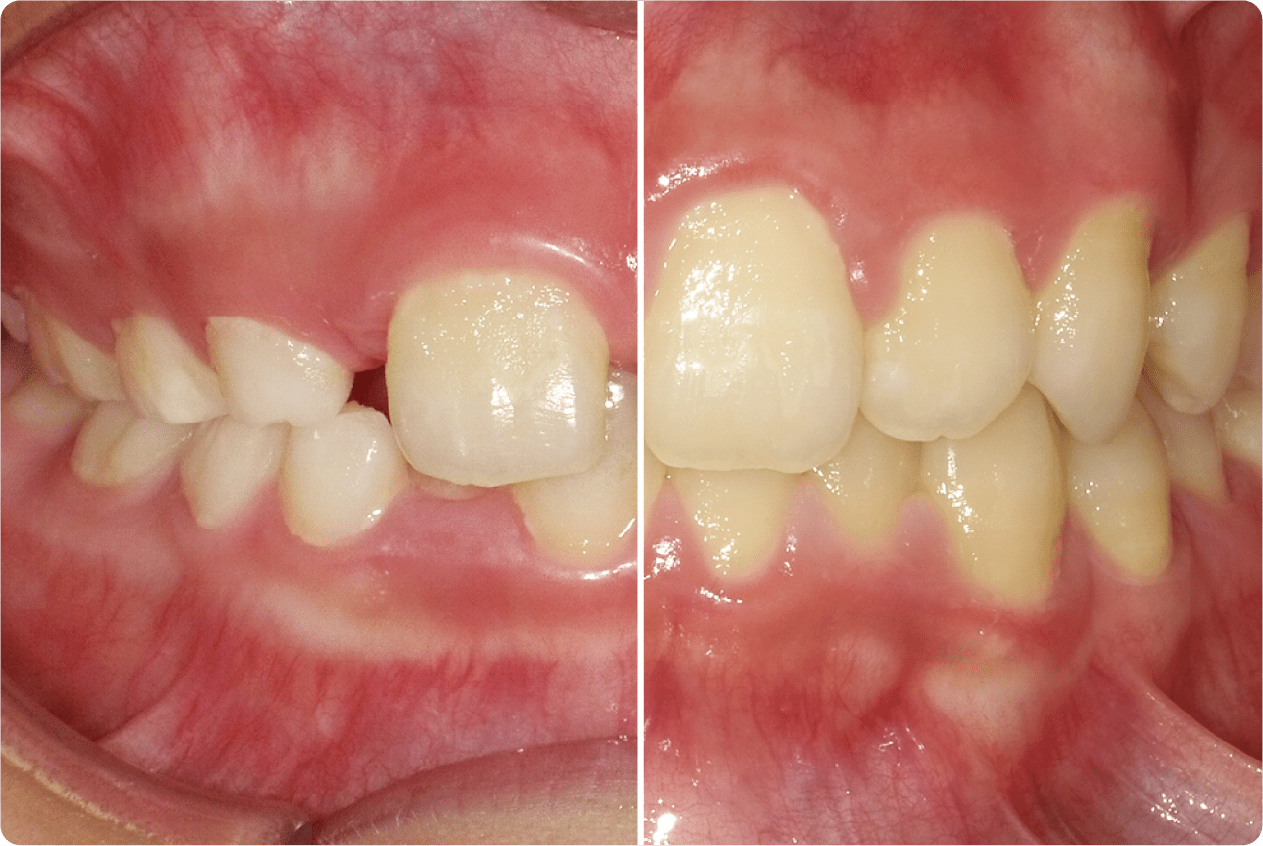

歯並びは成長に影響します!